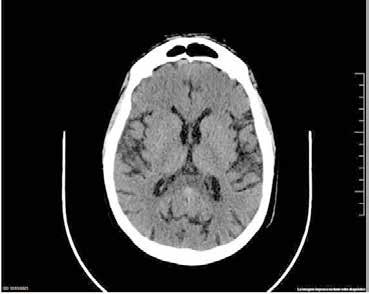

Se revisaron las pruebas solicitadas en Urgencias. En la analítica se en contró una hemoglobina (Hb) de 14 g/dl, un volumen corpuscular medio (VCM) elevado (106μ³) compatible con su historia de alcoholismo o con un déficit de ácido fólico o vitamina B12, una discreta elevación de la proteina C reactiva (13,2 mg/dl) sin elevación de otros reactantes de fase aguda y unas enzimas hepáticas dentro de la normalidad, con la aspartato transfe rasa ligeramente elevada 39 U/L (rango de normalidad: 5-34). Los tóxicos en orina fueron negativos, así como la etanolemia. La radiografía (rx) de tórax mostraba una condensación en el lóbulo superior izquierdo en posi ble relación con la infección tuberculosa diagnosticada en 2011 (Figura 1). La TC -a pesar de no mostrar signos de patología aguda intracraneal, ni masas ni signos de sangrado- sí que mostraba atrofia cerebral con surcos muy marcados, hallazgo no concordante con la edad de nuestro paciente (Imagen 2).

Figura 2.

TC craneal corte transversal. Aumento de la profundidad de los surcos en posible relación a signos de atrofia encefálica acentuada para la edad del paciente sin que se observen claras lesiones focales ni colecciones o signos de sangrado intra o extraaxial. Se observa una tenue hipodensidad del esplenio del cuerpo calloso.